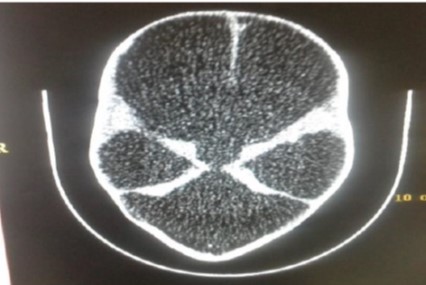

Hydranencephaly in a 2 months old infant with a working diagnosis of severe hydrocephalus

Thelma Prudence Oluwarotimi Eretan , Olaniyi Eretan, Rachael Akinola, Babajide Balogun

228-232